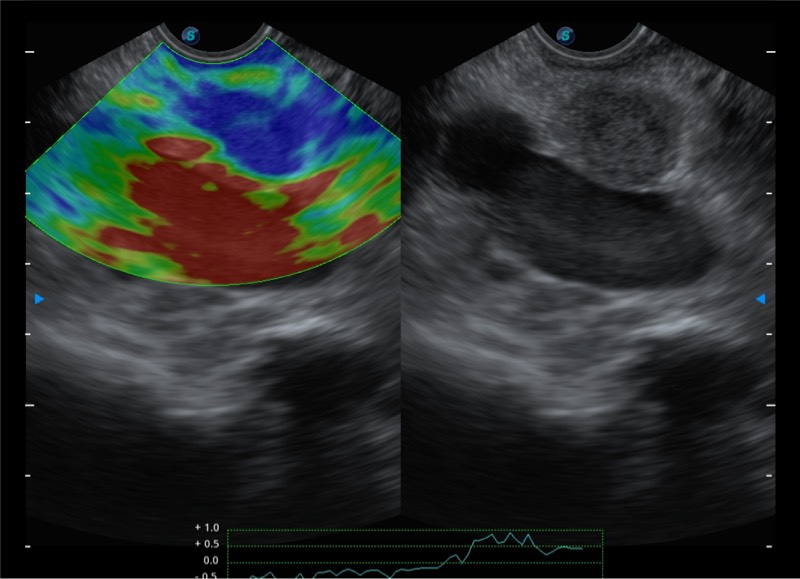

• 搭载百万级CMOS成像技术

• 及自主研发凸阵换能器,

• 可呈现优质的内镜和超声画面

基于二十年的超声技术积累,milan米兰提供了最新一代的独立超声主机,在提供高质量图像的同时满足多学科使用。具备常见多普勒技术并提供弹性成像、声学造影等高端影像技术。新一代传感器具有更强的抗干扰能力并减少图像伪影。